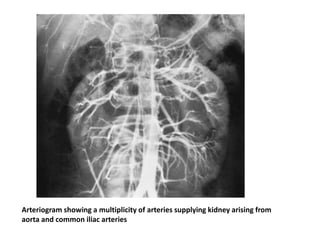

• Blood supply to the horseshoe kidney can be quite variable

Arteriogram showing a multiplicity of arteries supplying kidney arising from

aorta and common iliac arteries